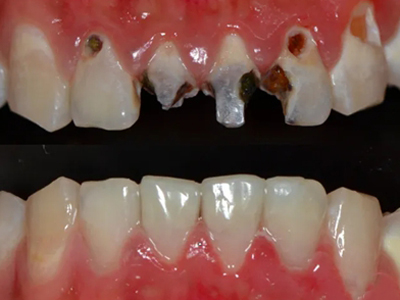

酸蚀症牙齿缺损严重有黑斑图

酸蚀症严重时会使牙齿出现大面积缺损,有三颗下牙损毁严重,露出不整齐的牙骨质边缘,几乎仅余留牙根。缺损处有黑斑,局部呈黄褐色,需积极就医进行牙齿修复。